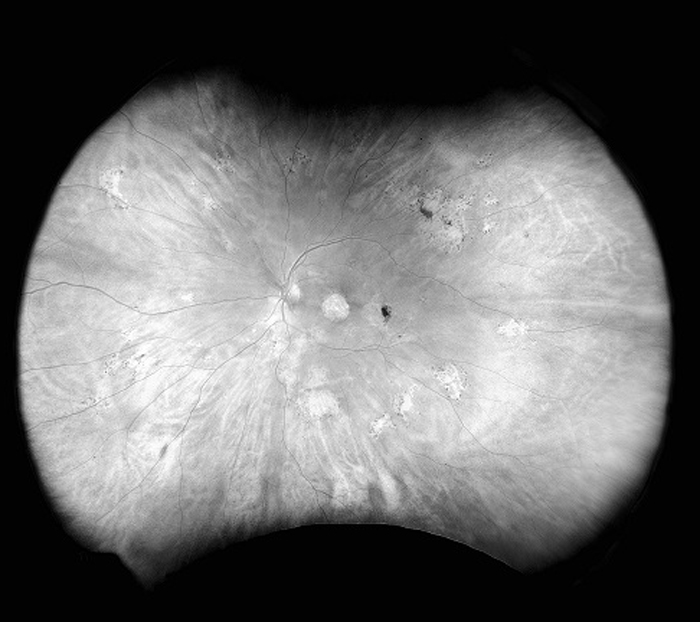

Silverstone est l’outil le plus performant du marché pour l’examen de la rétine. Le seul appareil d’imagerie de la rétine ultra-grand champ avec un OCT Swept-Source intégré, Silverstone produit une image optomap en une seule prise en moins d’½ seconde et permet un balayage par OCT guidé de l’ensemble de la rétine jusque dans la périphérie lointaine.

Silverstone offre les avantages suivants :

- L’ultra-grand champ avec OCT intégré Swept-Source facilite un examen détaillé de la rétine, du vitré à la sclère.

- L’OCT Swept-Source guidé ultra-grand champ permet de visualiser les pathologies en tout point de l’optomap.

- L’imagerie 3-in-1 color Depth™ permet d’obtenir d’importantes données cliniques, de la surface de la rétine à la choroïde.

| Modalités d’images | optomap couleur et optomap plus (laser rouge et vert) : Vue couleur composite Vue laser vert Vue laser rouge optomap af (laser vert) : autofluorescence optomap fa (laser bleu) : Fluorescéine (FA) optomap icg (Infra-rouge) : Vert d’indocyanine (ICG) Swept-Source Tomographie par cohérence optique (OCT) |